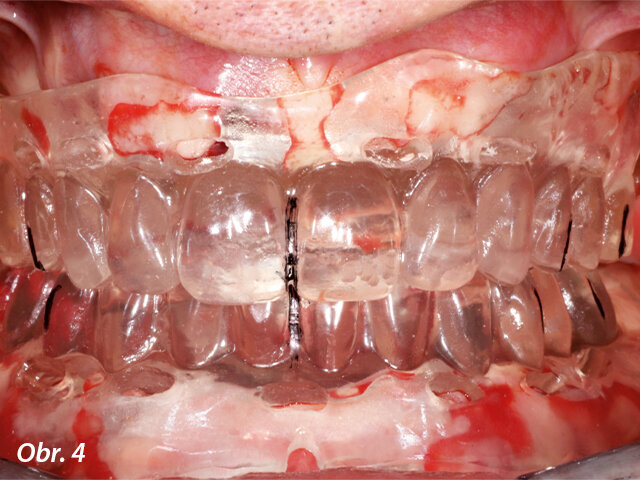

Na kliniku se dostavil 66letý pacient, klasifikovaný jako ASA II, stěžující si na bolest, mobilitu zubů a diskomfort v levé části horní čelisti. Klinické vyšetření odhalilo pokročilé onemocnění parodontu stupně C a fáze IV podle nové klasifikace periodontálních onemocnění. Bylo zjištěno spontánní krvácení, hnisání a celkově vysoký stupeň zánětu.10 Pacient měl metalokeramické korunky v dolní čelisti a tři různé můstky v horní čelisti. Všechny byly extrémně mobilní, a to mezi stupněm II a III. Panoramatický RTG snímek ukázal difúzní a pokročilý stupeň resorpce kosti zasahující ke všem zbývajícím zubům (obr. 1). V horní čelisti byly čtyři implantáty, dva z nich s hlubokými kostními defekty kolem fixtur. CBCT sken potvrdil diagnózu zubů stanovenou pomocí panoramatického RTG snímku a prokázal velký hluboký kostní defekt v rozsahu od špičáku až za první levý premolár a velmi malou výšku kosti pod levou i pravou stranou dna sinu (obr. 2). Levá strana sinu vypadala téměř celá zaplněná zánětlivou hyperplazickou tkání.

CBCT sken zachycující dno sinu a sníženou výšku kosti na obou stranách horní čelisti.